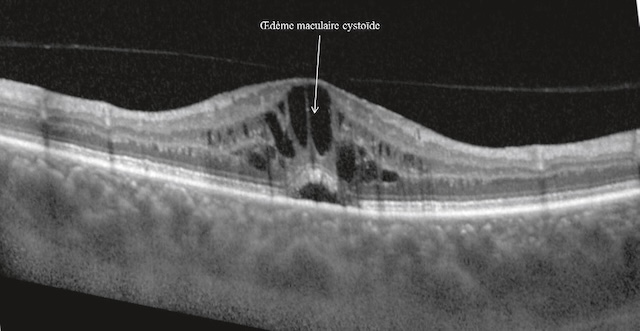

2 2324Aspect du fond d’œil normal (fig. 1.36)

a Examen du pôle postérieur

Cet examen amène à décrire trois éléments principaux :

Le fond d’œil présenté ici montre une vue nette de la rétine gauche avec ses structures bien visibles. À droite de l’image, la papille optique se distingue par sa couleur claire et arrondie, point d’émergence des vaisseaux rétiniens qui se ramifient en direction des différentes zones de la rétine. Vers la gauche, on remarque une zone plus pigmentée, la macula, avec en son centre un point légèrement plus sombre : la fovéola. L’ensemble du champ rétinien est uniformément orangé, sans tache ni lésion apparente. Les deux vues, dont l’une est annotée, permettent d’identifier précisément les régions essentielles de l’œil, utiles pour évaluer l’état général de la vision centrale et périphérique.

- • la papille, qui correspond anatomiquement à la tête du nerf optique (et à la tache aveugle à l’examen du champ visuel), et qui est formée par la réunion des fibres optiques. Elle se présente comme un disque clair à bords nets, comportant une excavation physiologique au fond de laquelle apparaissent l’artère et la veine centrales de la rétine;

- • les vaisseaux rétiniens qui se divisent pour vasculariser la surface rétinienne interne. Les branches veineuses sont plus sombres, plus larges et plus sinueuses que les branches artérielles dont elles suivent grossièrement le trajet;

- • la macula (fovéa), située à proximité et en dehors de la papille. Région très riche en cônes, elle permet la vision des détails; c’est une zone ovalaire d’environ 1,5 sur 1 mm (taille sensiblement identique à celle de la papille). Elle est centrée par une zone avasculaire ne contenant que des cônes, zone essentielle permettant la vision des détails, apparaissant plus sombre, de 400 µm de diamètre, et appelée fovéola.